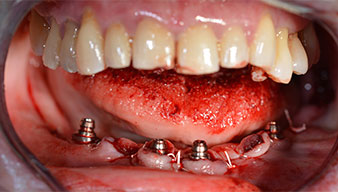

Angled abutments (35°) were screwed in to compensate for the divergence of the distal implants, with the result that the emergence profile of all implants was as perpendicular as possible to the bite plane. This is a prerequisite for occlusal placement of the provisional and subsequently the permanent denture (Fig. 15 and 16).